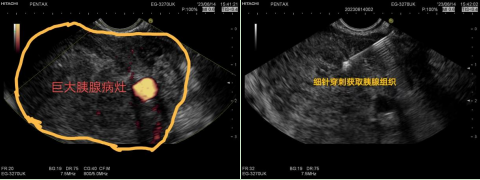

一名反复腹痛合并腹水的患者住入消化内科求医,CT显示胰腺占位病变,但是病变位置较深,临床上怀疑恶性肿瘤,却无法迅速获取病理诊断。马师洋教授仔细查看患者及病例资料后,提出了为该患者做超声内镜引导下细针穿刺技术(EUS-FNA)的建议。6月14日下午,在洛阳市中心医院病理科黄建伟主任及王猛医师现场病理支持下,马师洋教授为患者进行胰腺扫查,仔细观察病变大小,评估病变性质及病灶周围情况,找到合适穿刺部位,精准的穿出目标组织条,为患者后续治疗拿到了关键的病理证据,整个过程仅用时30分钟。

马师洋教授入驻洛阳市中心医院消化科两个月以来,带领消化团队取得了不俗的成绩,特别是在超声内镜检查及其介入治疗方面,更是填补了医院的空白。EUS-FNA的成功开展,标志着我院消化内镜技术又一重大突破,真正补齐了消化内镜“3E”技术,标志着洛阳市中心医院消化内镜技术迈入了国内先进行列。